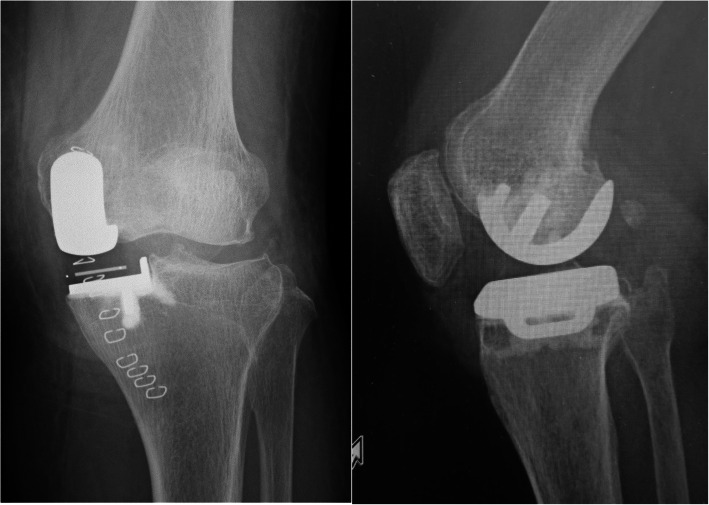

Fig. 4.

Radiographs of case 1 after the revision surgery

At 13 months postoperatively, she had sudden and severe knee pain while asleep. She could not walk, so she had to be brought to our facility in an ambulance. The meniscal bearing was posteriorly dislocated, as shown on the radiographic images (Fig. 2). We could not succeed in closed reduction; therefore, we performed surgical intervention. During the revision surgery, we observed the subsidence of the femoral component. The femoral component could easily be retrieved because of the loosening of the femoral component. In addition, there was no bone attached to the undersurface of the retrieved femoral component (Fig. 3). We implanted the same small-sized cemented Oxford femoral component, and the 8-mm thick bearing was inserted (Fig. 4). One year after the revision of UKA, her knee was pain-free and had a ROM of 0° extension to 140° flexion. She had no femoral migration and bearing re-dislocation.